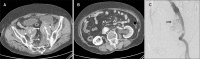

Arterioureteral fistula is a rare but life-threatening condition. An endovascular treatment approach is commonly used; however, there is a potential risk of infection. We present a case in which a patient presented with abdominal pain and was diagnosed with a ruptured internal iliac artery aneurysm and a subsequent arterioureteral fistula. An aortic stent graft was inserted to treat the arterioureteral fistula, but it subsequently became infected, resulting in the patient's death. This case underscores the importance of early diagnosis and treatment of arterioureteral fistula and the possibility of graft infection.